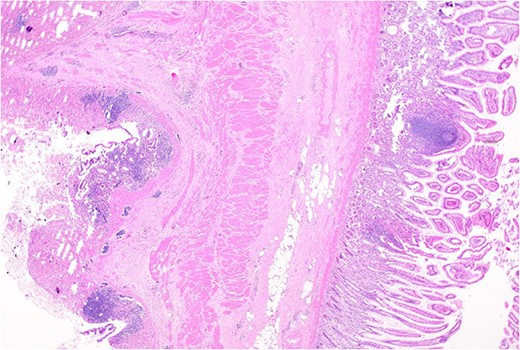

Histopathology macroscopically identified a 42-mm cystic caecal mass adjacent to the ileocaecal valve (Figs 4–5). Microscopic examination revealed a duplication cyst involving the ileal and colonic tissue comprised of a complete duplication of the colonic wall including mucosa, submucosa and muscularis propria, which was shared with the involved colon (Fig. 6). There was no mucosal connection to adjacent normal bowel. There was some ulceration with inflammatory changes in the overlying mucosa suggestive of prior cyst perforation and areas of attenuated villiform mucinous epithelium with features of low grade dysplasia (Figs 7-8). Special stains for organisms (Periodic Acid-Schiff (PAS), Fredericamycin A (FMA), Ziehl-Neelsen (ZN) and modified ZN) were negative. There were no granulomas, heterotopic mucosa or evidence of malignancy. Twenty-nine lymph nodes were identified with no evidence of malignancy.

Remnant of normal colonic epithelium (left) within the duplication cyst that shares common muscularis propria with the terminal ileum (right), low power.